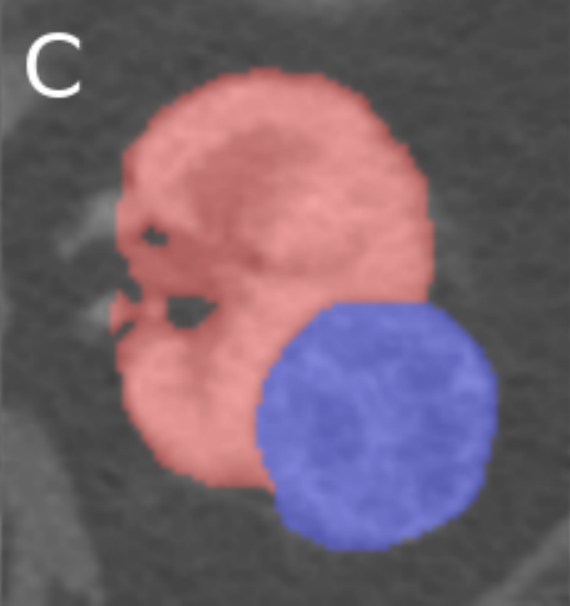

Fed-KITS2019.

The KiTS19 dataset  [heller2020state, heller2019kits19] stems from the Kidney Tumor Segmentation Challenge 2019 and contains CT scans of 210 patients along with the segmentation masks from 79 hospitals. We recover the hospital metadata and extract a 6-client federated version of this dataset by removing hospitals with less than 101010 training samples. The task consists of both kidney and tumor segmentation, labeled 1 and 2, respectively, and we measure the average of Kidney and Tumor DICE scores [dice1945measures] as our evaluation metric.

The preprocessing pipeline comprises intensity clipping followed by intensity normalization, and resampling of all the cases to a common voxel spacing of 2.90x1.45x1.45 mm. As a baseline, we use the nn-Unet library [isensee2021nnu] to train a 3D nnU-Net, combined with multiple data augmentations including scaling, rotations, brightness, contrast, gamma and Gaussian noise with the batch generators framework [isensee2020batchgenerators]. Appendix G provides more details on this dataset.

Appendix G Fed-KiTS19

The KiTS19 dataset  [heller2020state, heller2019kits19] stems from the Kidney Tumor Segmentation Challenge 2019 and contains CT scans of 210 patients along with the segmentation masks from 77 hospitals666It is important to note that KiTS19 dataset does not come with the hospital information. We obtained the data distribution per client from one of the organizers of this challenge, Nicholas Heller, over email communication. We acknowledge the help of Nicholas Heller for sharing this valuable resource with us that helped us explore federated learning strategies with this dataset for the first time.. We only consider the training dataset of this challenge as the segmentation masks are not provided for the test dataset. We recover the hospital metadata and extract a 6-client federated version of this dataset by removing hospitals with less than 101010 training samples. Figures 4(a) and  4(b) show the repartition of patients per client before and after this client selection respectively. Table 7 provides further details of the train and test split at each selected client.

G.4 Task

The task consists of both kidney and tumor segmentation, labeled 1 and 2, respectively. The background is labeled as 0. The score we consider on this dataset is the average of Kidney and Tumor DICE scores [dice1945measures].

Refer to caption

(a) Original KiTS19

(b) Fed-KiTS19

Figure 4: Patient distributions across hospitals of the original KiTS19 Dataset and the derived Data distribution of Fed-KiTS19